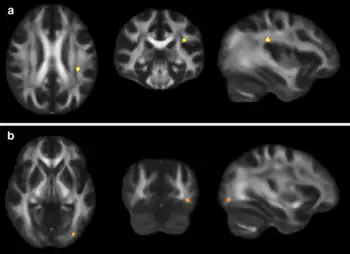

Increased diffusion on MRI is associated with the severity of post-concussive symptoms